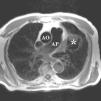

Seudoaneurisma ventricular izquierdo.

Left ventricular pseudoaneurysm